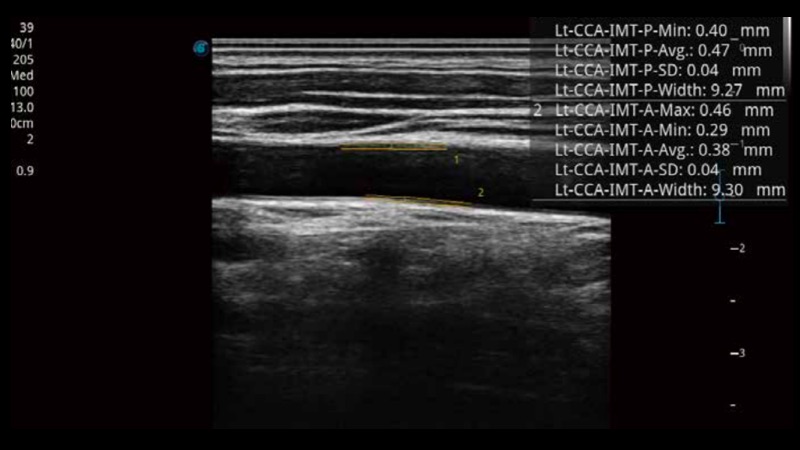

• 血管内中膜自动测量Auto IMT

自动识别前后壁内膜厚度,为心血管疾病早期评估提供快速准确依据。